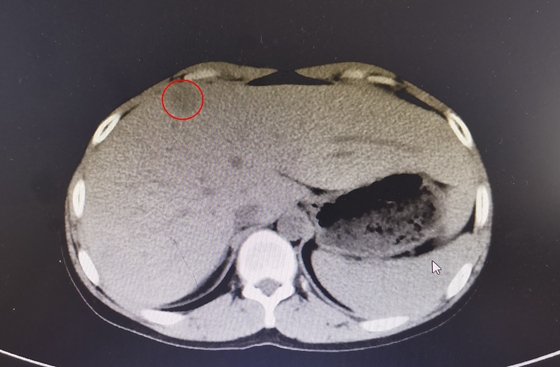

影像资料显示小哲肝脏明显肿大